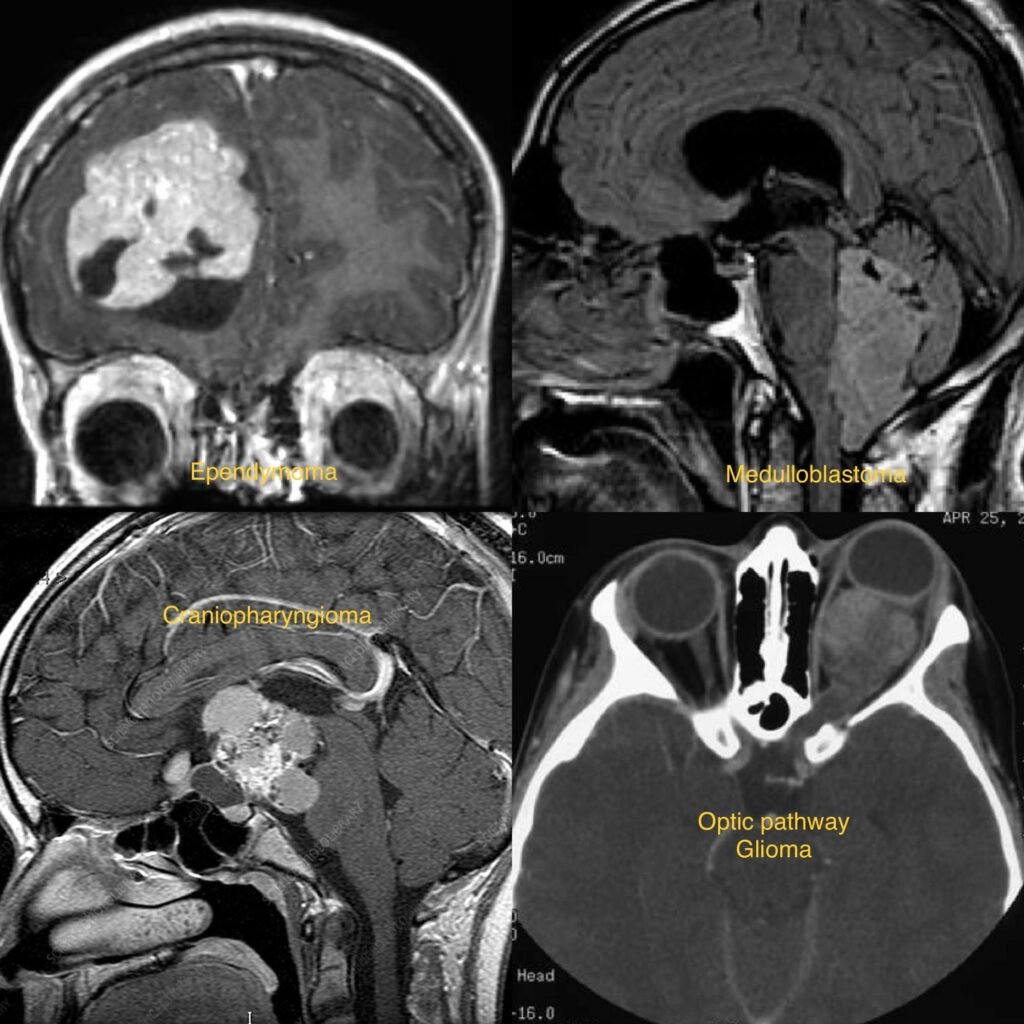

Pediatric Brain Tumors

Pediatric Brain Tumors are abnormal growths of cells in the brain or central nervous system that occur in children and adolescents. These tumors can be benign (non-cancerous) or malignant (cancerous), and they can arise from various types of brain tissue. They are the most common solid tumors in children.

- Diagnosis typically involves a thorough neurological examination, medical history, imaging studies such as MRI or CT scans, and sometimes biopsy to determine the type and grade of the tumor.